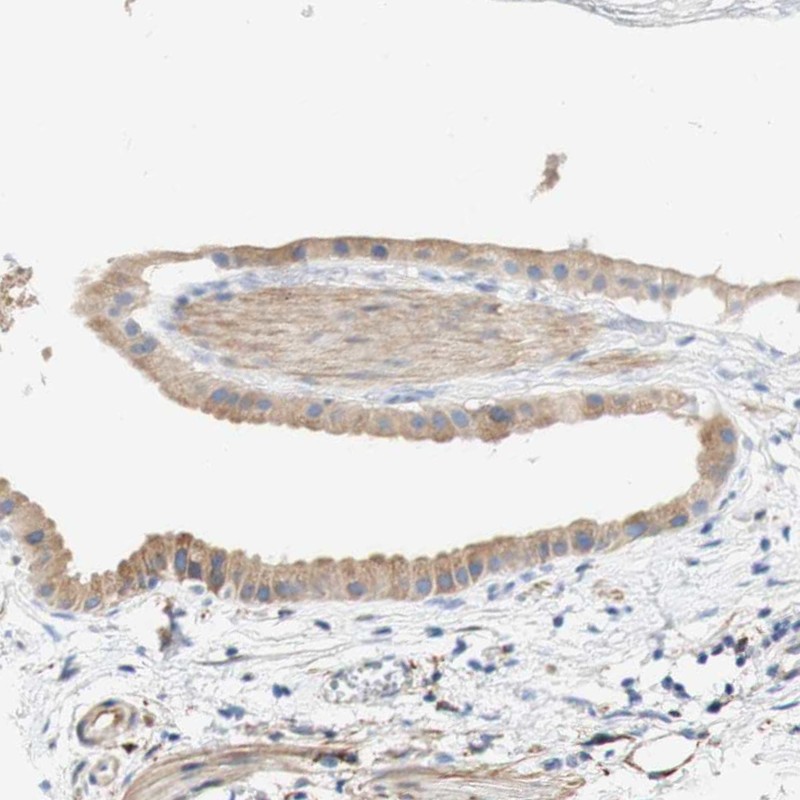

Immunohistochemical staining of human gallbladder shows weak cytoplasmic positivity in glandular cells.